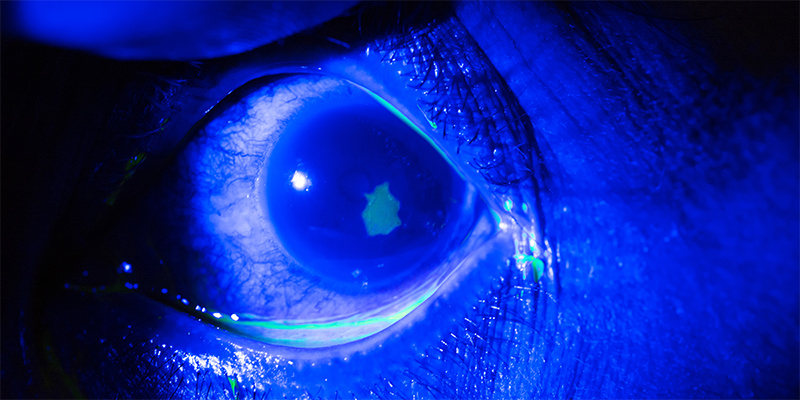

De NHG-Standaard Rood oog en oogtrauma adviseert om eenmalig een antibiotische oogzalf aan te brengen bij een traumatische cornea-erosie. Deze aanbeveling is echter met name gebaseerd op expert-opinion. Een recente cochranereview laat zien dat er tot nog toe geen bewijs is dat profylactisch antibiotica een ooginfectie voorkomt of het genezingsproces versnelt.